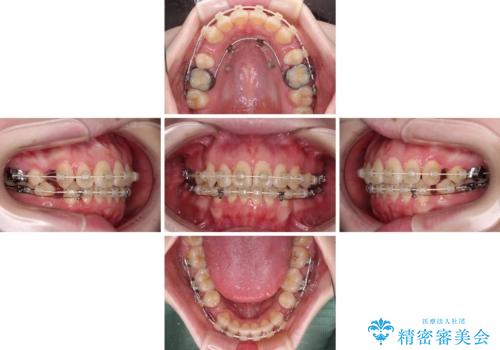

- 審美装置

- 2年9ヶ月

- 30回以上

上顎前歯をしっかりと後方に移動させるため、口蓋側にアンカースクリューと補助装置を併用し、上下左右の第一小臼歯4本を抜歯し、ワイヤー装置にて矯正治療を行うこととしました。